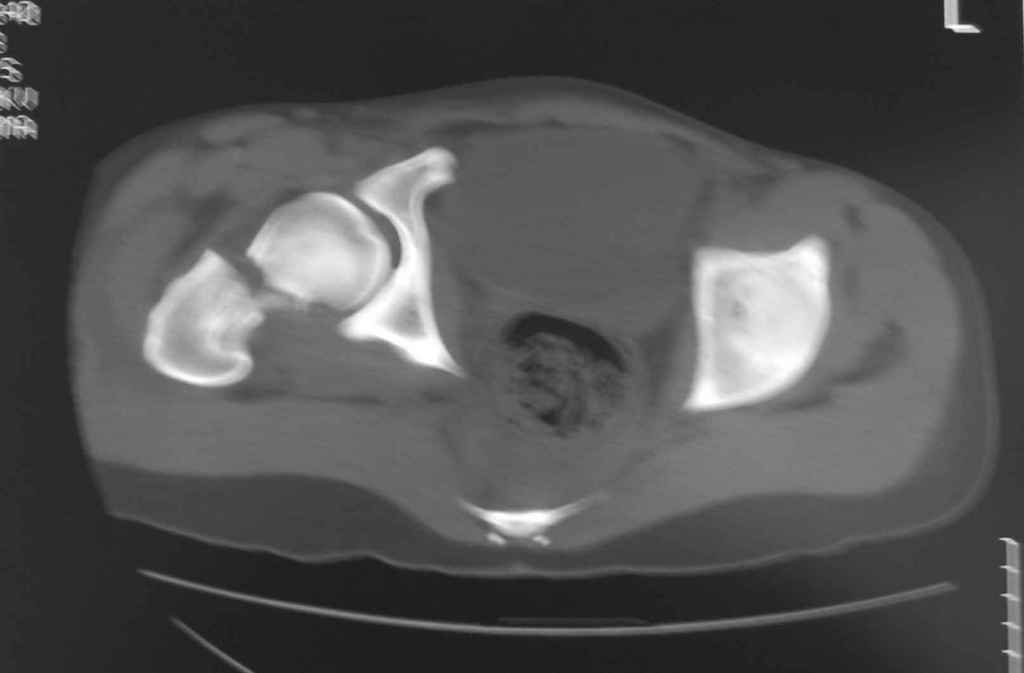

Уважаемый Алексей, на представленных Вами снимках имеется вертикально-нестабильное повреждение тазового кольца без повреждения вертлужной впадины. Учитывая это, а так же растущий возраст ребенка я бы выбрал аппарат внешней фиксации в виде кольцевой опоры, т.к. не смотря на оскольчатый перелом крыла в переднем отделе можно ввести минимум 2 стержня + 1-2 надвертлужно. Этого будет достаточно чтобы "зацепится", выполнить репозицию и дальнейшую фиксацию. Перелом шейки по моему лучше прооперировать 3 канюлированными винтами по АО.

Perelom golovki bedra nado bylo operirovat srochno 2 boltami ( vtechenii 8 chasov posle pereloma!!!).

Шейку срочно закрыто винтами.

Таз - подвздошным и падлобковым доступом раздельные рекострукционные пластины 4 штуки. Сплошную пластину как у взрослых нельзя (из-за роста придется доставать)